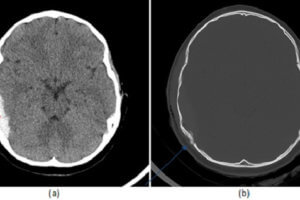

Diffuse Axonal Injury

The third T in the 3T trauma framework (see cases on epidural hematoma and penetrating trauma) refers to “other targets” and concerns delayed complications of traumatic brain injury. These competitions include hydrocephalus,... Read more »